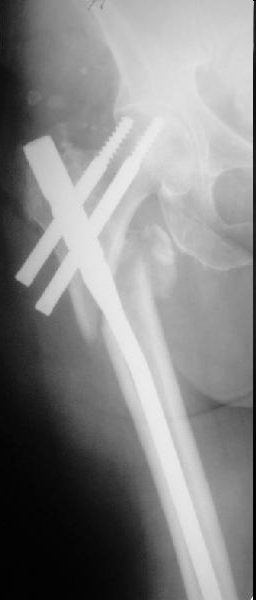

Это типичная проблема, вот аналогичный случай. Удалили, исправили,

фиксировали другим PFN.